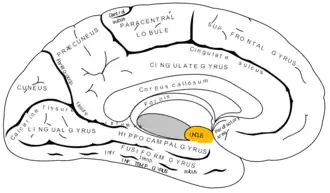

Medial surface of left cerebral hemisphere. Uncus is shown in orange. | |

The uncus is an anterior extremity of the parahippocampal gyrus. It is separated from the apex of the temporal lobe by a sulcus called the rhinal sulcus.[1] Although superficially continuous with the hippocampal gyrus, the uncus forms morphologically a part of the rhinencephalon.